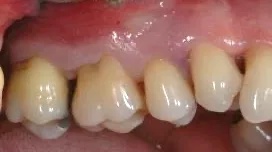

Selon les situations cliniques, il sera possible de préserver la situation initiale de la gencive et donc l’esthétique du sourire.

Ces chirurgies permettront de conserver les dents sur plusieurs années grâce à un suivi professionnel.

Des techniques chirurgicales de préservation papillaire permettent de régénérer les tissus parodontaux en garantissant leur maintien esthétique. Ces techniques chirurgicales avancées s’effectuent sous aides optiques grossissantes et avec des instruments micro chirurgicaux spécifiques.